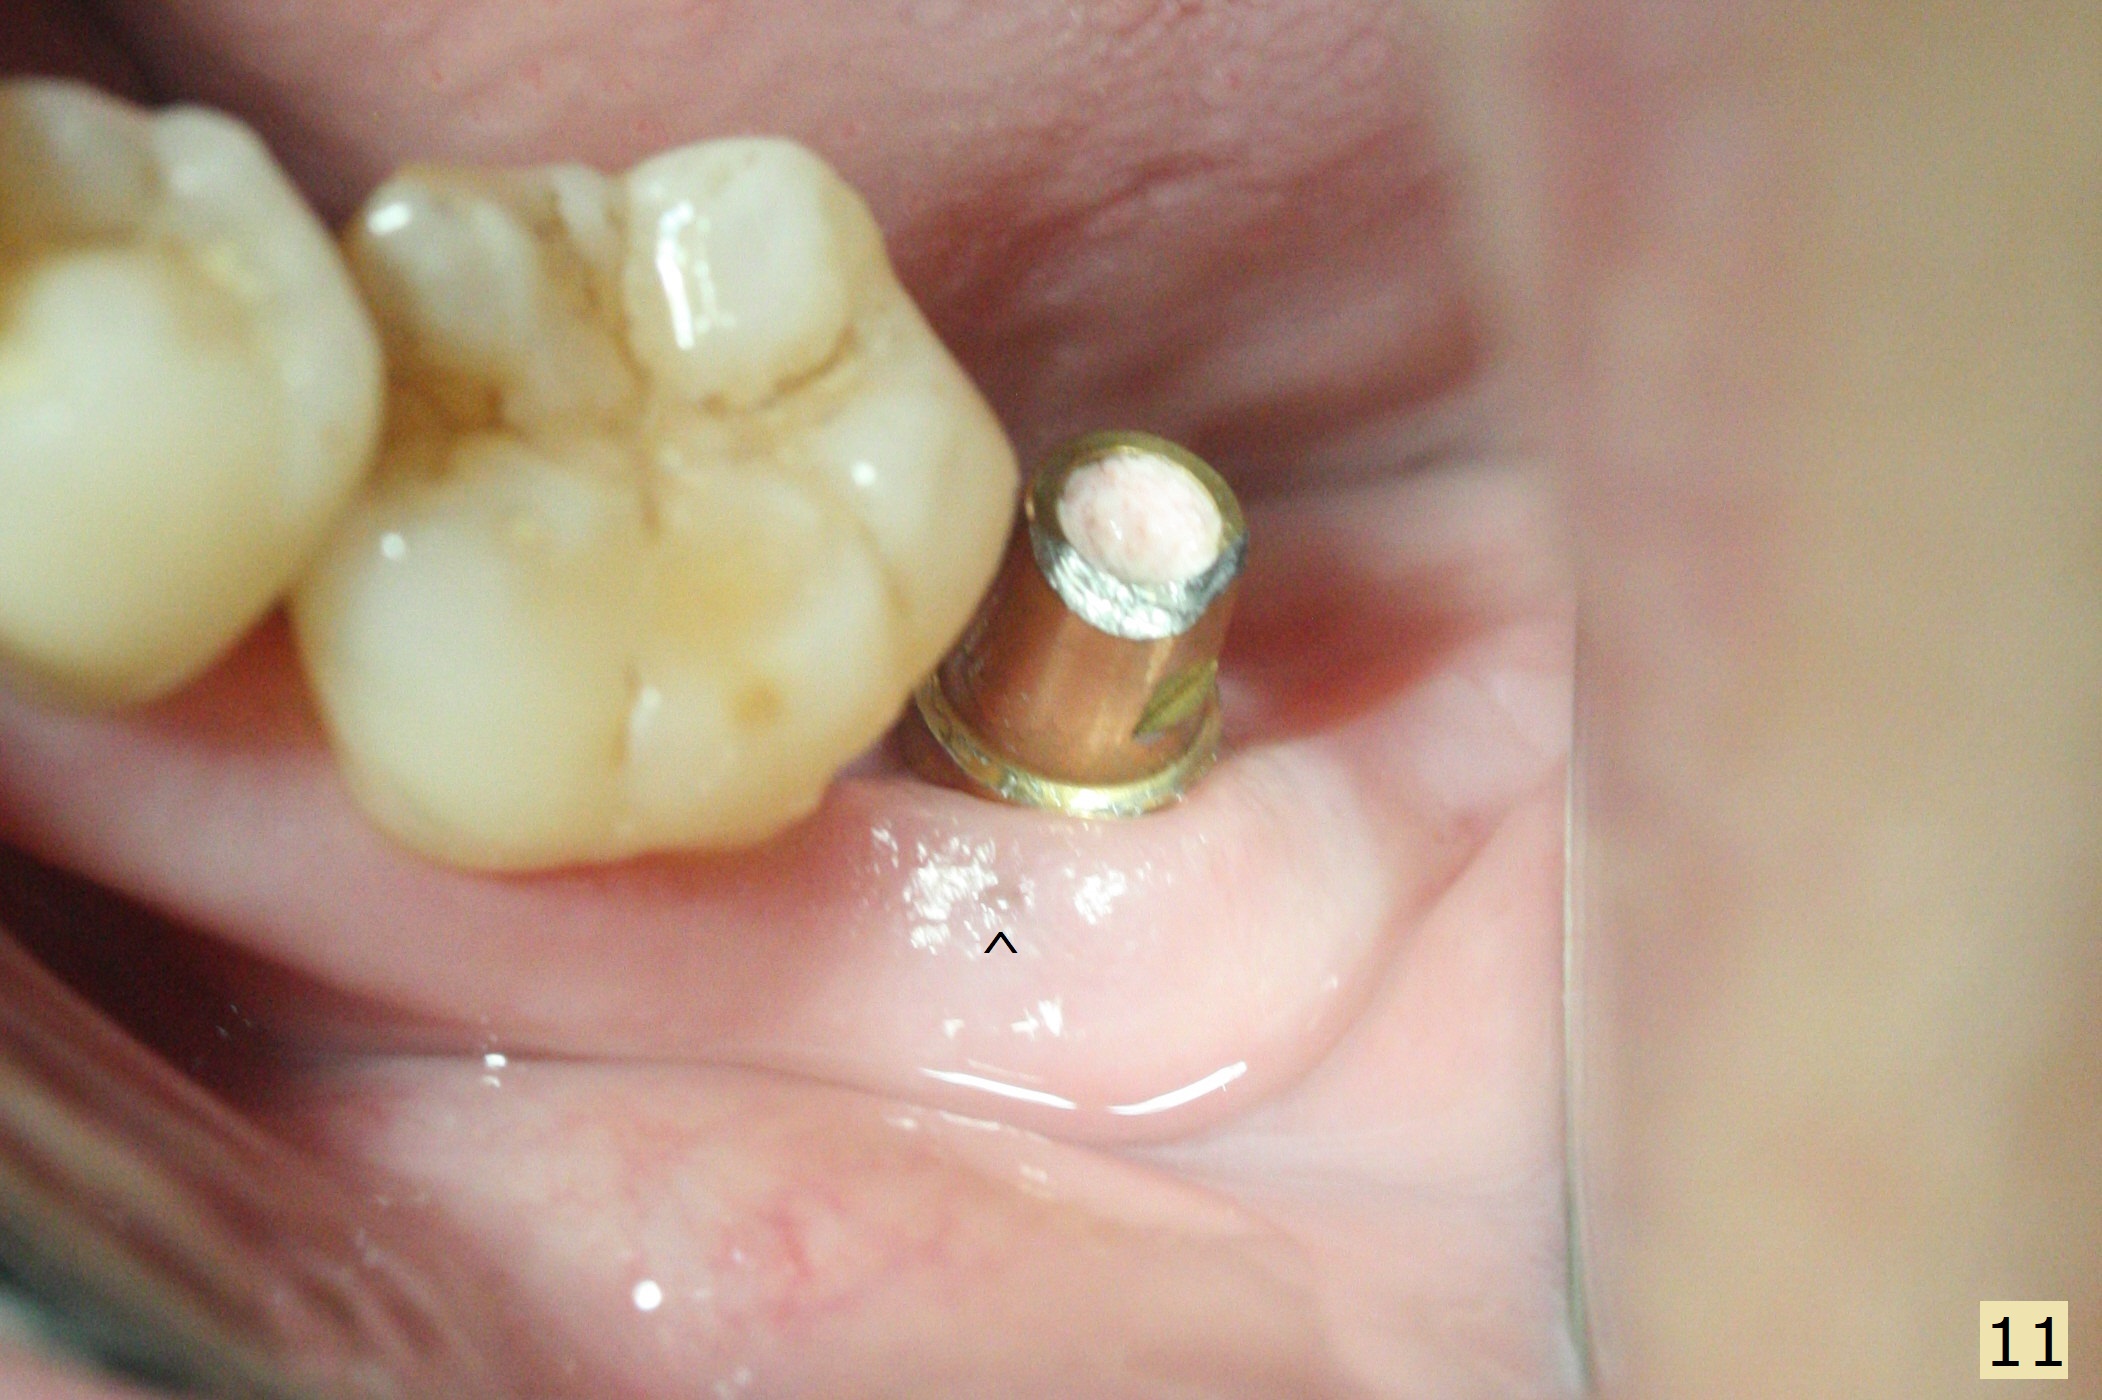

Socket shield (partial extraction therapies) is going to be conducted in this case to form a substitute buccal plate of the 2nd molar (Fig.1 *). The apex of the shield that contacts the 4.5x10 mm dummy implant cannot be removed because of poor access (Fig.2 * (12 mm offset)). Due to high bone density, a 4.5 mm drill has to be used in order to place a 5x7.3 mm definitive implant (Fig.3). In spite of the fact that the implant seems to be completely seated, the implant is ~ 1 mm supracrestal lingually. After implant removal, a 4.5x11.5 mm drill cannot reach the depth due to high bone density. 800 RPM instead of 50 RPM may help. When the implant is reseated, it appears to be .5 mm deeper than before clinically, although it looks incompletely seated in X-ray (Fig.4 <). The insertion torque is 60 Ncm. Allograft mixed with PRF is placed around the implant with cover screw, particularly mesiolinguodistal (Fig.4 *). The sockets of #17 and 18 are approximated with the help of 2 piece of PRF and collagen plug. The wound dehisces 9 days postop (Fig.5,6), although asymptomatic. Forced closure of the sockets with suture seems unnatural. An immediate provisional should have been fabricated. CT shows possible loss of part of bone graft (Fig.7). Regraft seems necessary in the appointment of uncover. Antibiotic is prescribed for another week. The gingiva seems healthy around the exposed healing screw 16 days postop (Fig.8). After debridement, the healing screw is then changed to a 4.5x5 mm healing abutment. The majority of the bone graft is lost without immediate provisional in 4 months (Fig.9 * (<: socket shield)). Then a 5.5x5 mm healing abutment is inserted for impression next appointment. A 5.2x4.5(4) mm cemented abutment is placed before impression (Fig.10). With socket shield (Fig.11 ^), the buccal gingiva looks more keratinized than the lingual one (Fig.12 *). Photos are taken immediately pre-cementation. Socket shield (*) covers the implant and abutment buccally (Fig.13 CT taken immediately pre-cementation).